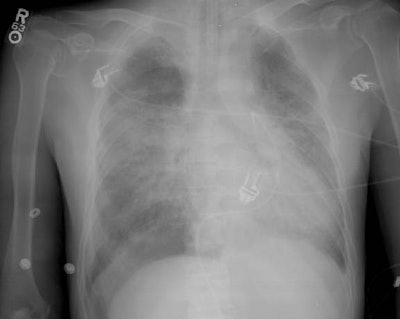

The images below are from a patient in the intensive care unit. The patient was admitted for radiation pneumonitis following radiation therapy for bronchogenic carcinoma. There is an endotracheal tube, and a Swan-Ganz catheter which was placed via a femoral venous approach.

On the initial film, the right costophrenic sulcus was cut off the film, but was suspicious for a "deep sulcus sign"- an indication of a pneumothorax in a supine patient. A repeat examination (below initial image) was performed which nicely demonstrated the "deep sulcus" on the right, as well as a pleural line in the right upper lung indicating that the pneumothorax had enlarged in the interval between the two films. This case demonstrates the need to include the costophrenic angles on all portable films.

Initial image: